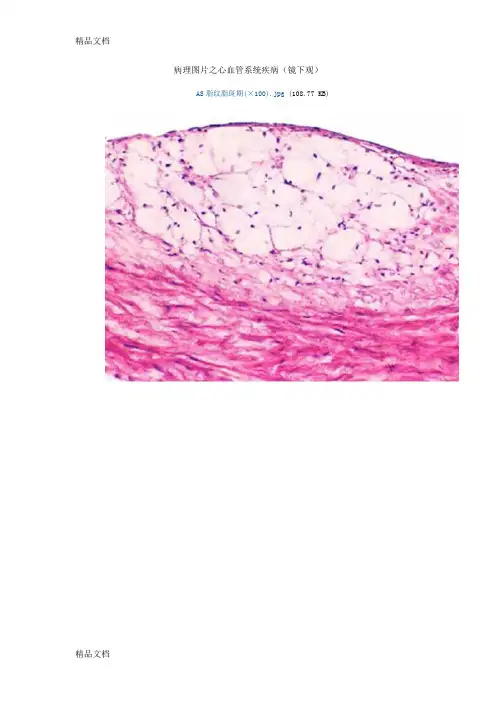

血管性水肿疾病图谱